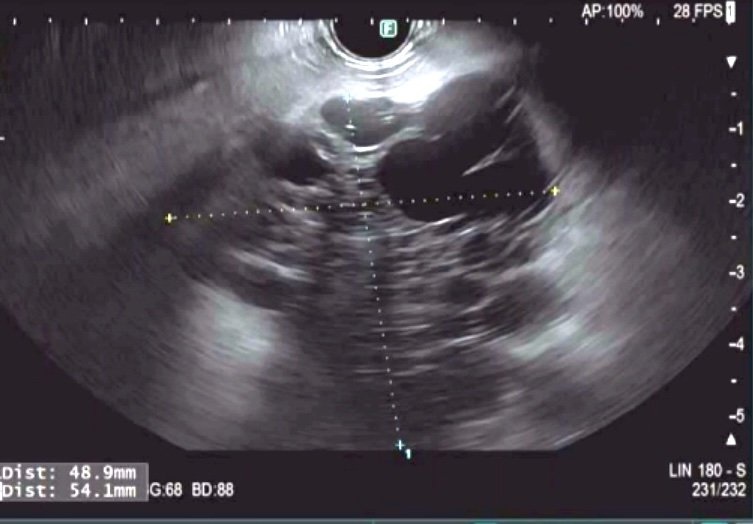

🟢 Cases from our #CLIMB Study @som_krishna. 70s 👵 5.4 cm multilocular cyst in HOP. Fluid FNA: Gluc 188, CEA < 4, VHL. EUS below ⬇️ nCLE video ▶️ below ⬇️: Fern-patern Vascularity MicroBx: Serous Cystadenoma